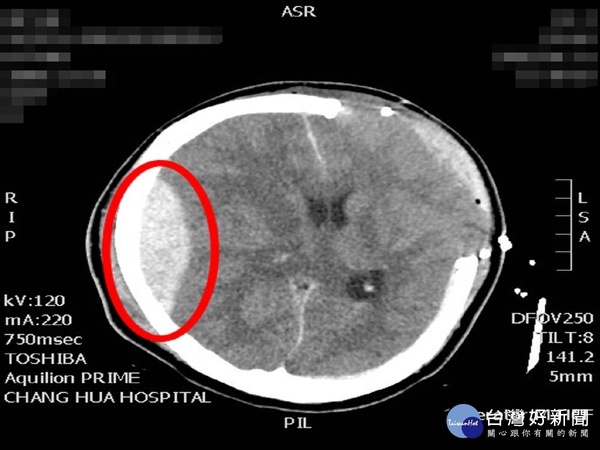

神經外科醫師張昕煥指出,患者到院時身上沒有明顯嚴重外傷,但左瞳孔放大,昏迷指數也只有3,懷疑腦部受到重創,果然在電腦斷層掃描後看到左側硬腦膜下腔有出血併嚴重腦腫現象,必須馬上接受開顱手術取出血塊才有機會保命。

張昕煥表示,患者的顱內壓升高且右邊瞳孔放大,再次電腦斷層掃描後發現,這次換成右側的硬腦膜上腔出血並擠壓到腦部,必須再次手術,但家屬擔心短時間內執行兩次腦手術負擔太大,遲遲不肯下決定,直到他和家屬說,術後昏迷指數能從3分進步到6分實屬罕見,很有希望繼續進步後才同意手術。